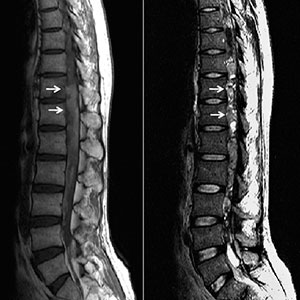

Las deformidades de la columna vertebral son alteraciones morfológicas de la misma que ocurre en sus tres dimensiones y que pueden ser producidas por diversas causas.La columna vertebral posee curvaturas  anteroposteriores normales para ayudar a soportar las cargas y que se encuentran en equilibrio. En el plano transversal la columna no presenta curvaturas, su presencia indica una deformidad llamada Escoliosis.

Este tipo deformidades requieren  estudios como radiografía, espinografía, resonancia, tomografía y otros estudios según el caso que nos ayudan a diagnosticar, definir la severidad de la deformidad vertebral, alteraciones asociadas, madures esquelética y con ello definir el mejor tratamiento en cada caso.